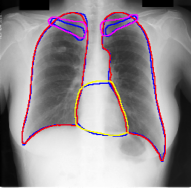

For each of these three datasets, we use three noise settings, denoted by , and . and are two settings synthesized by our Markov process with (expansion) and (shrinkage), respectively. Figure 4 shows examples of our synthesized label noise. We also include the mix of random dilation and erosion noise used by previous work (Zhu et al., 2019; Zhang et al., 2020b; a). This is achieved by randomly dilate or erode a mask with a number of pixels. Note that our Markov label noise can theoretically include this type of noise by setting . Detailed parameters for these settings are provided in the Appendix.

Table 1 shows the segmentation results of different methods with synthetic noisy label settings on JSRT , ISIC 2017 and Brats 2020 dataset. Note that QAM cannot be applied to Brats 2020 dataset because their network is designed for 2D only. We compare DICE score (DSC) on testing sets (against the clean labels). For each setting, we train 5 different models, and report the mean DSC and standard deviation. In and , where biases show up in noisy labels, the proposed method outperforms the baselines by a big leap in total case. The compared methods, however, only work when little bias is included, like . is equivalent to setting in our Markov model, resulting in . We also test the proposed method on real-world label noise, results shows in Table 2. Figure 5 shows examples of label correction results. We provide more qualitative results in the Appendix A.4.